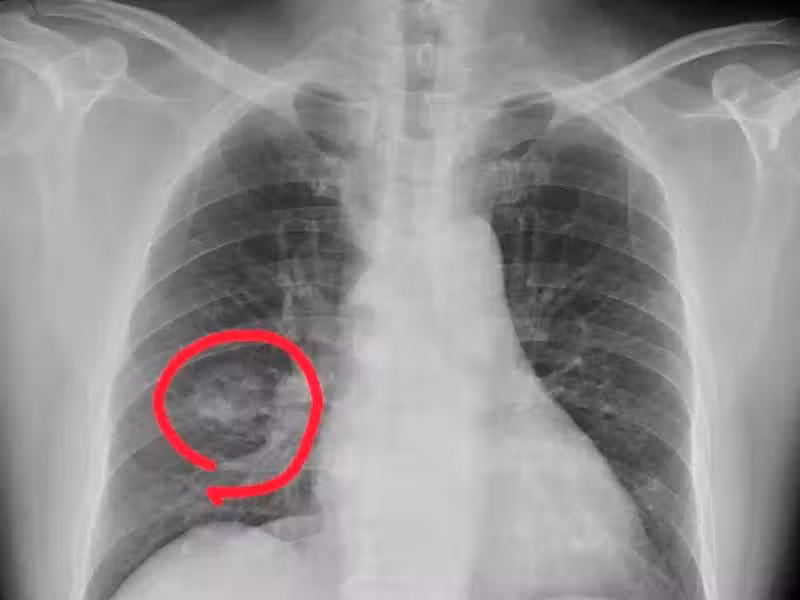

肺癌來臨並非無聲無息,提醒:手腳出現 4 種異常,可能是肺癌到來,不要大意!

1. 手指變粗

一般情況下手指變粗很可能是肺癌的信號,尤其是長期吸菸的男性朋友,要特別警惕杵狀指,也就是手指末端變粗,增生,膨大,同時還會伴有咳血、刺激性乾咳、胸痛等癥狀。